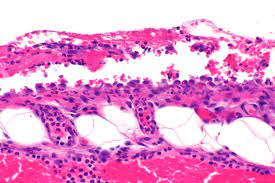

심낭염은 심장 주위의 막인 심낭(pericardium)이 염증을 일으키는 상태를 나타냅니다. 심낭은 심장을 둘러싸고 있는 얇은 막으로, 심장을 보호하고 안정시키는 역할을 합니다. 하지만 여러 가지 이유로 인해 심낭 주위에 염증이 발생하면 심낭염이라고 합니다.